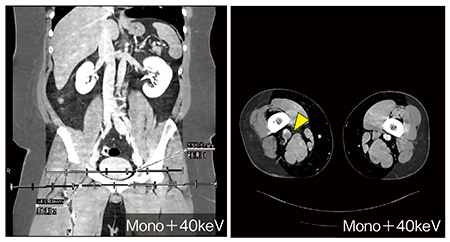

30歳代,男性。身長185cm,体重170kgとかなり大柄である。捻挫に対してシーネ固定中に下肢腫脹があり,近医を受診した。CTにて腋窩部の深部静脈血栓症(DVT)が認められたものの中枢側の状態は画質が不十分で不明であり,治療方針決定のため当院でのCT再撮影依頼となった。当院でDVT目的での撮影では,体重換算上350mgI製剤で250mLが必要となるが,製剤として最大量である135mLでの対応と仮定すると,造影剤量は必要量の約半分となり,造影剤量も線量も足りない。そこで,造影効果を向上する2つの低エネルギー撮影法(70kV Dual PowerとDual Energy)のそれぞれのメリット,デメリットをあらかじめ検討した上で,本症例ではDual Energy撮影を実施した。

CT Venographyを見ると120kV相当のmixed imageではコントラストが低く血栓を除外しにくいが,仮想単色X線画像を作成するアプリケーションの“DE Monoenergetic Plus(Mono+)”で再構成した40keV画像を使用することでコントラストの向上により十分な評価が可能であり(図6),不必要なフィルタ留置などを避ける意味で臨床的に有益な情報を提供できた。

図6 症例5:深部静脈血栓症におけるMono+の40keV画像を用いた評価